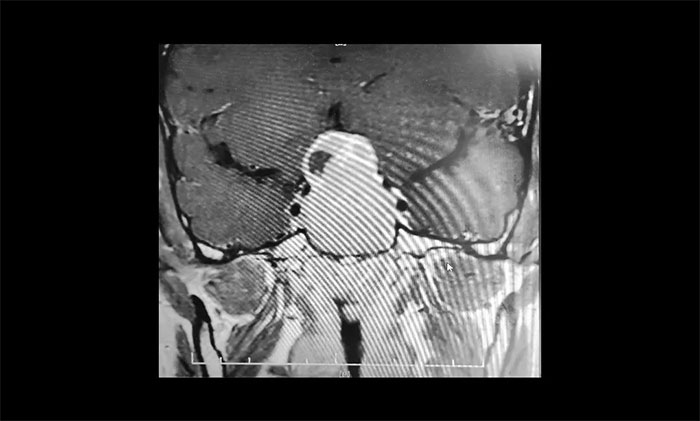

▲ 术前影像:巨大垂体瘤,向鞍上生长

为了进一步确定瘤体的位置和大小,当即进行了鞍区MRI平扫+增强。影像显示,蝶鞍显著扩大,鞍区见一“塔样”肿块灶,病变总矢横高径约3.5×4.5×5cm。瘤体向鞍上生长,占据鞍上池,明显推移视交叉、分界模糊,三脑室前下部受压变形。鞍底塌陷、蝶窦填充;侵及包绕两侧海绵窦约1/2,海绵窦向外侧移位。

结合影像检查,潘仁龙主任、李士其教授会诊后一致达成共识。由于巨大垂体瘤长期压迫视神经,患者视物出现异常,右眼已经失明,手术指征明显,应尽快手术,尽可能挽救患者视力。